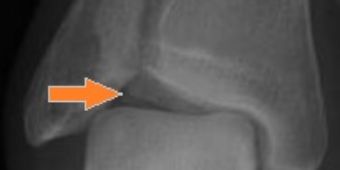

knochenauswuechse

Knochenauswüchse (Pfeil) am oberen Sprunggelenk.

Dieses Krankheitsbild wird auch als soccer player´s ankle (Fußballer Sprunggelenk) bezeichnet, da bevorzugt Sportler bei langjähriger Belastung im Rahmen von Kontaktsportarten wie Fußball, erkranken. Dabei bilden sich je nach Ausmaß des Impingements (d.h. der Einklemmung) knöcherne Auswüchse am Schienbein und später auch am Sprungbein im vorderen Sprunggelenkabschnitt (Bild oben). An diesen Knochenvorsprüngen klemmen Weichteile wie Gelenkschleimhaut, Narben und Kapselanteile ein.

impingement-tibiaosteophyt

Fräse (li.) mit der große Knochenvorsprünge (Pfeil) entfernt werden. © Asklepios

Therapie: kleine Fräsen führen zum Erfolg

Im Rahmen eines arthroskopischen Eingriffes kann der überschießende Knochen mit speziellen Instrumenten und Fräsen  (Bild) abgetragen werden, was die Beweglichkeit wieder verbessert und die Schmerzen beseitigt. Im Idealfall erfolgt die operative Therapie, bevor irreversible Knorpelschäden auftreten.